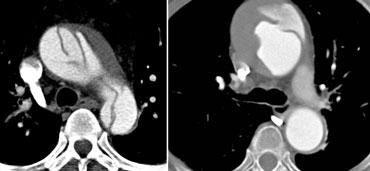

Bóc tách type A lan vào các động mạch thân cánh tay đầu. TRÁI: Không thấy khi tiêm ở tay trái. PHẢI: Cùng bệnh nhân khi tiêm ở tay phải.

- Tiêm thuốc cản quang ở tay PHẢI: không có thuốc cản quang đi qua phía trước các nhánh bên của quai động mạch chủ, tránh làm méo hình ảnh vạt nội mạc (hình minh họa)